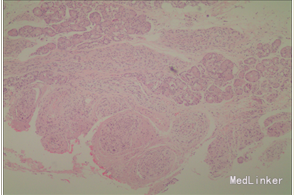

诊断 处理

完善相关检查,在气管插管麻下行“左额眶部占位病变切除术”。术后病理诊断为“(左眼眶)丛状神经纤维瘤”。术后给予患儿脱水、营养脑神经、抗感染等对症治疗。复查CT未见明显异常。

患儿术后2周左眼睑下垂较术前好转。双侧瞳孔反射、眼球活动均无异常。 丛状神经纤维瘤主要发生于眼睑,在出生后或幼年时期即出现症状和体征。侵袭范围广泛,包括眼睑、眶内软组织、眶骨和邻近的脑、颞部等。眼部最早和最多见为上、下睑软性肥厚,皮下瘤组织增生,使上、下睑隆起。眼睑皮肤常有淡棕色色素斑,眼球向前突出和向下移位。眼球突出虽然很显著,但向眶内纳入并不困难。肿瘤组织可直接侵袭眶内各种结构,上睑提肌首先被波及,引起上睑下垂,上举不足或不能。MRI可准确显示病变的范围尤其显示病变与邻近结构的关系,也可清楚显示其他部位伴发的肿瘤,但难以清晰显示眶壁骨质改变。手术治疗是必要的,手术切除应注意以下问题:1.眼睑病变的切除;2.眶内病变的处理;3.提上睑肌的处理;4.眶骨缺失的处理。丛状型术前诊断容易,但治疗较为棘手,易复发。